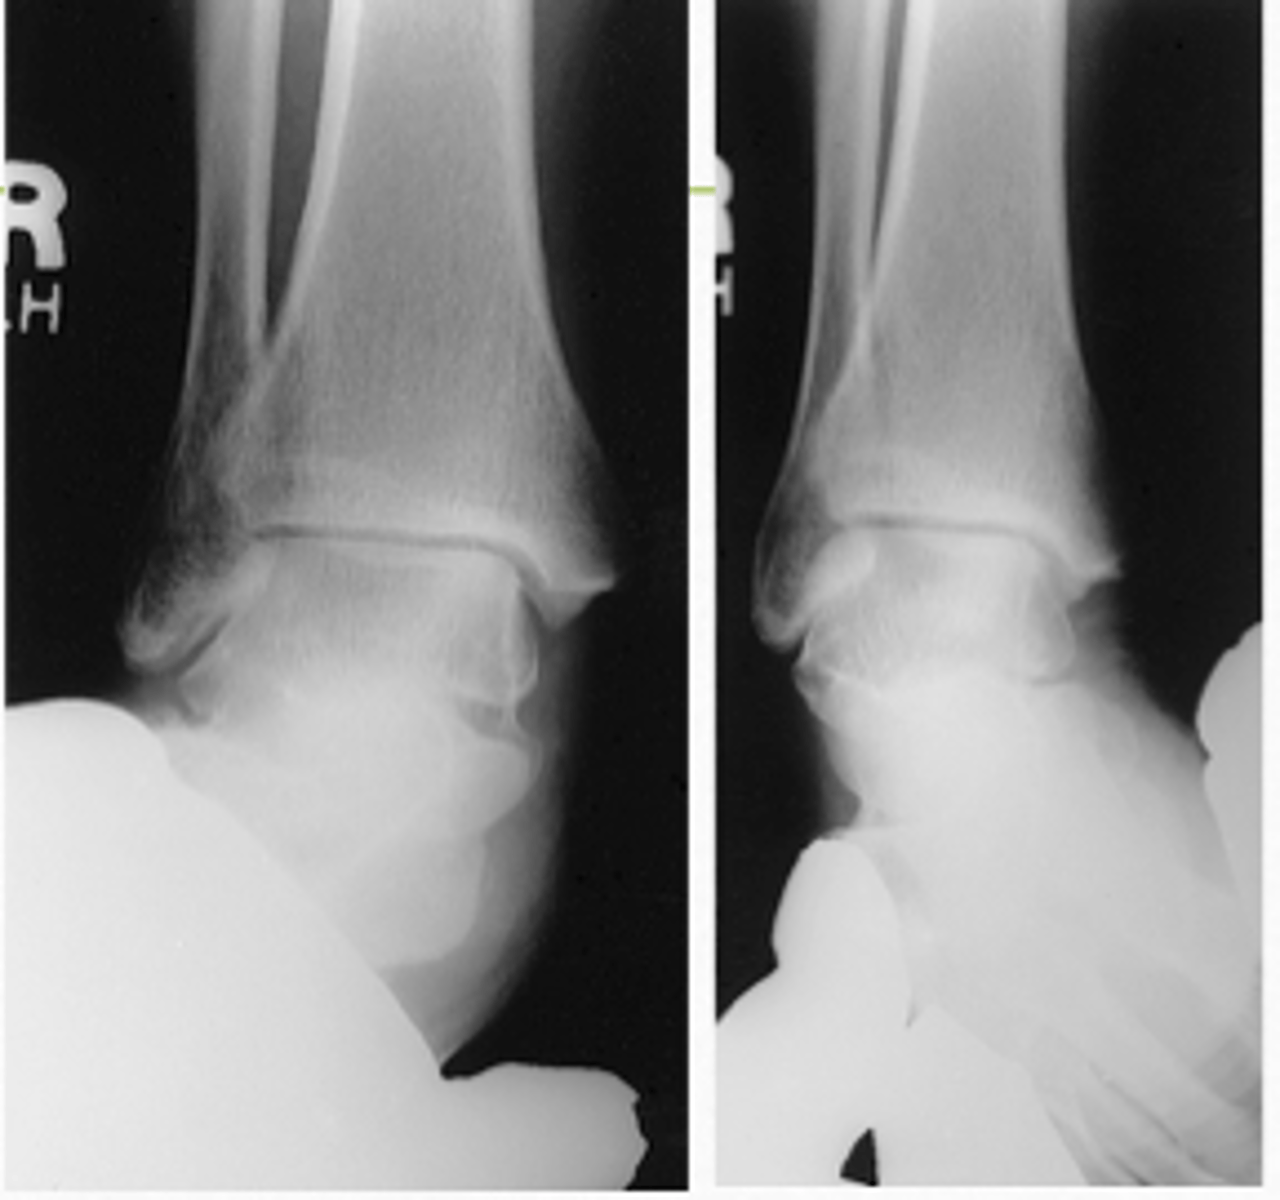

AP Stress Ankle (Inversion)

What projection is this?

AP Stress Ankle (Eversion)

Evaluation Criteria AP Stress Ankle

- Distal aspect of tibia and fibula demonstrated

- Ankle joint to center of collimation field

- Optimal exposure factors